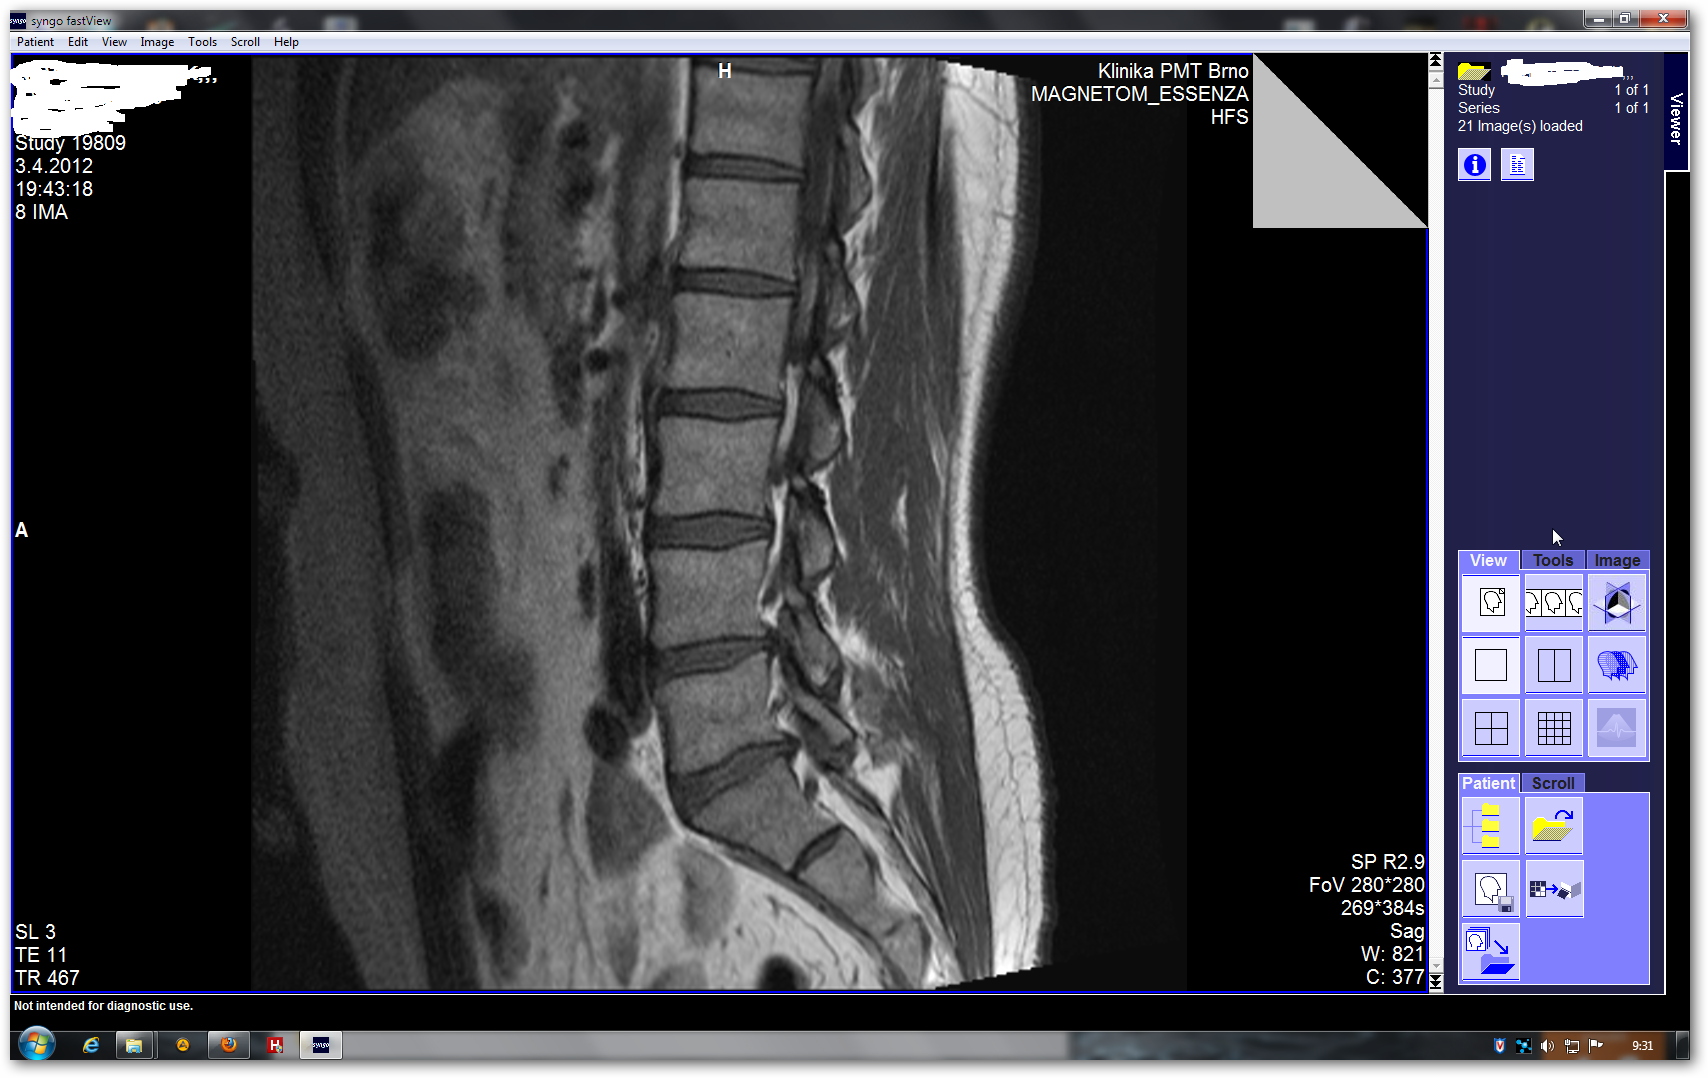

Zkoušel jsem přetáhnout složky,vytvořit obraz disku,použít Shrink.Obrázky se zobrazí pouze pokud mám DVD v mechanice.Domnívám se,že to nefachčí,protože bych potřeboval ten samotnej sofware.Ten jsem nikde ke stažení nenašel(pochopitelně).Každej ten snímek z obr8 jde zvetšit a pomocí kolečka mysi se posunuje po krocích,takže má v sobě dalších cca 10 fotek.(obr 9a10)

Vyhřezla mi ploténka,pokud nepujdu na operaci a zrehabilituji to.Tak chci mít snímky i v práci,až mi tam zas jebne a povezou mě do špitálu,at ví v čem je problém.Co jsem tak postřehl za poslední čtvrt rok,je u nás lékařská věda pěkně v hajzlu.